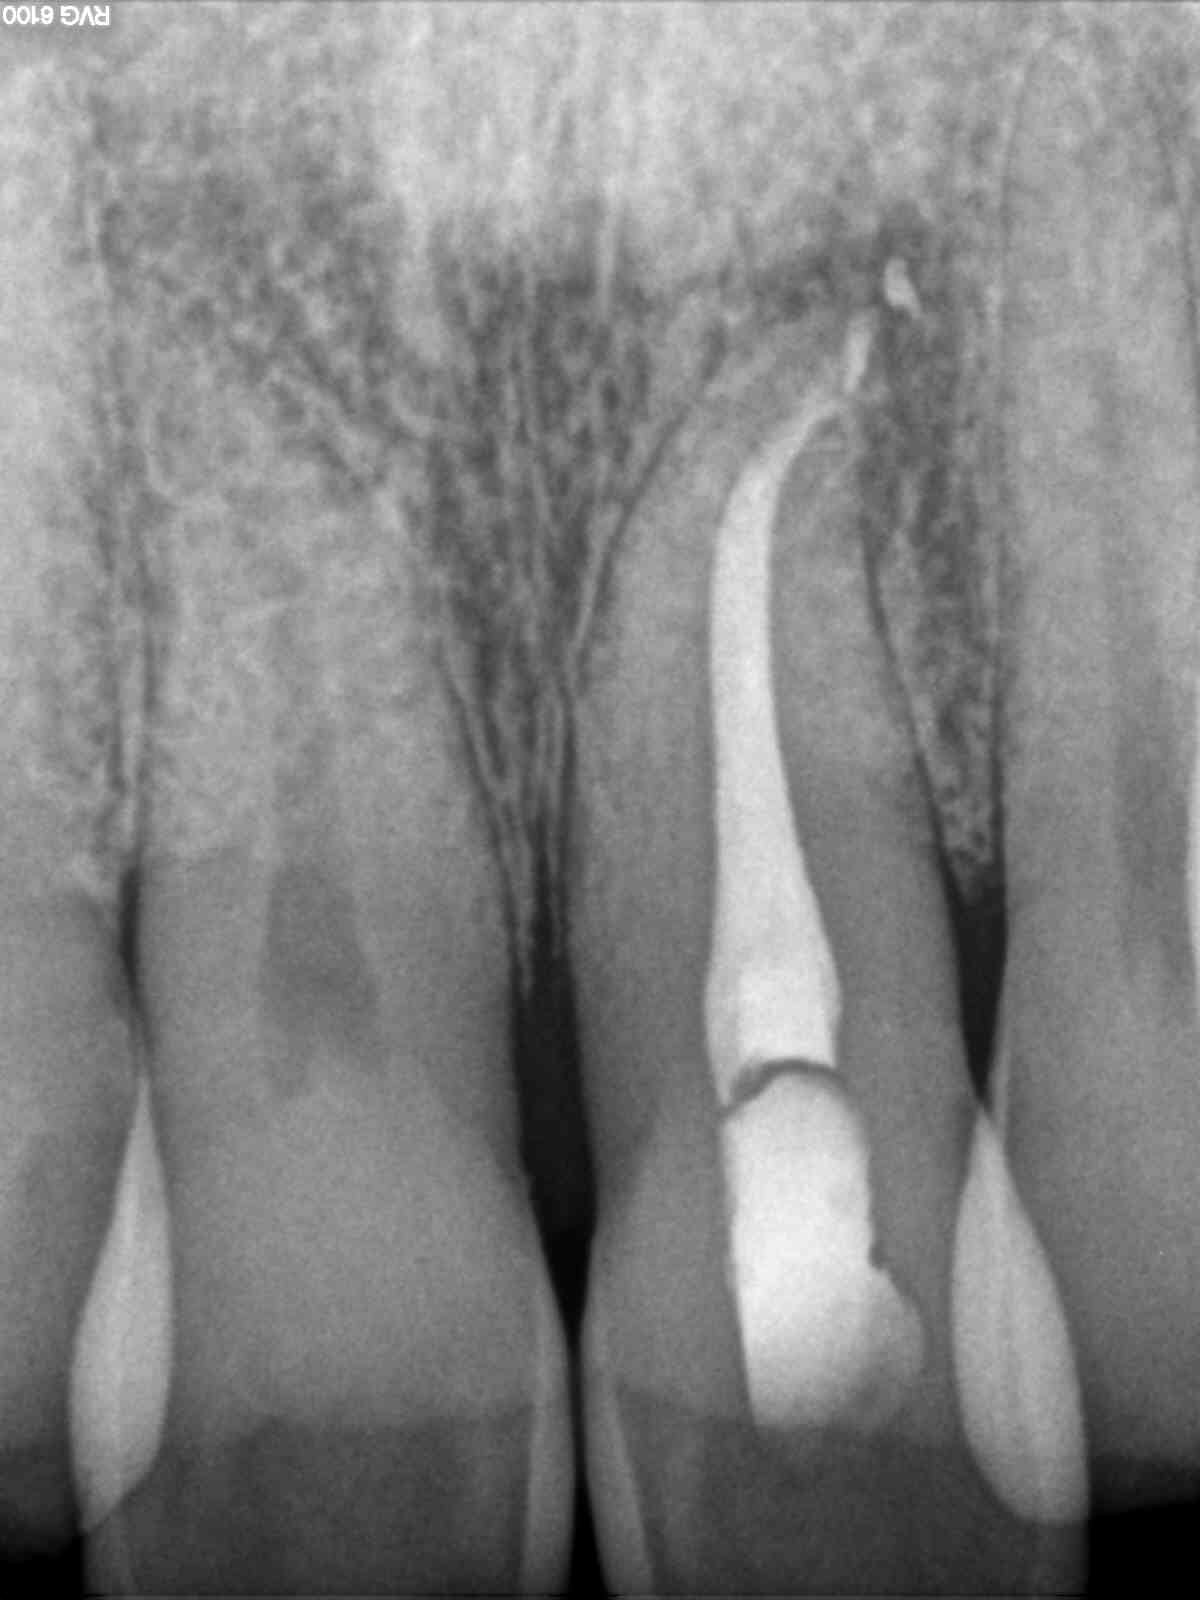

Evaluamos el caso con un CBCT

Una vez todo estudiado, preparamos el caso: